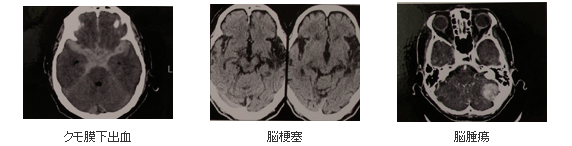

この検査では患者さんが寝台に横になるだけで、苦痛なく頭部の断層像(輪切り)が鮮明に撮れてます。特に、らせん状に連続してデータを収集することができ(ヘリカルスキャン)従来の装置により短時間( 1分~4分)で広範囲の検査が行えます。日本人の3大疾患にあたる脳卒中の多くは、前ぶれもなく突然発症し、後遺症をもありえる非常に恐ろしい病気です。

当院の CT装置では、立体的に三次元画像(3D)でみることができ、脳出血、脳梗塞、脳腫瘍など頭部疾患の診断において、絶大な効果を発揮します。脳ドックなどの詳しい検査内容は医師へおたずねください。